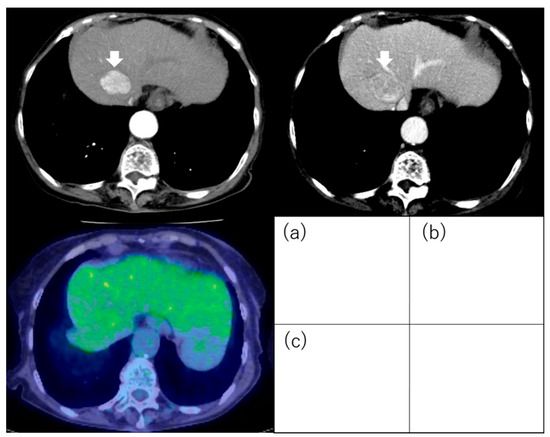

5. 18F-Fluorodeoxyglucose Positron Emission Tomography

5.2. 18F-Fluorodeoxyglucose Uptake

- Ida, Y.; Tamai, H.; Shingaki, N.; Shimizu, R.; Maeshima, S.; Maekita, T.; Iguchi, M.; Terada, M.; Kitano, M. Prognostic value of (18)F-fluorodeoxyglucose positron emission tomography in patients with small hepatocellular carcinoma treated by radiofrequency ablation. Cancer Imaging Off. Publ. Int. Cancer Imaging Soc. 2020, 20, 74. [Google Scholar] [CrossRef]

| Ida et al. [85] | 121 | ≤3 tumors and ≤3 cm | RFA | Outcome (recurrence, OS) | PET positivity was one of the independent factors for metastatic recurrence (HR, 10.297; 95% CI, 3.128–33.898; p < 0.001) and OS (HR, 7.300; 95% CI, 1.920–27.751; p = 0.004). |